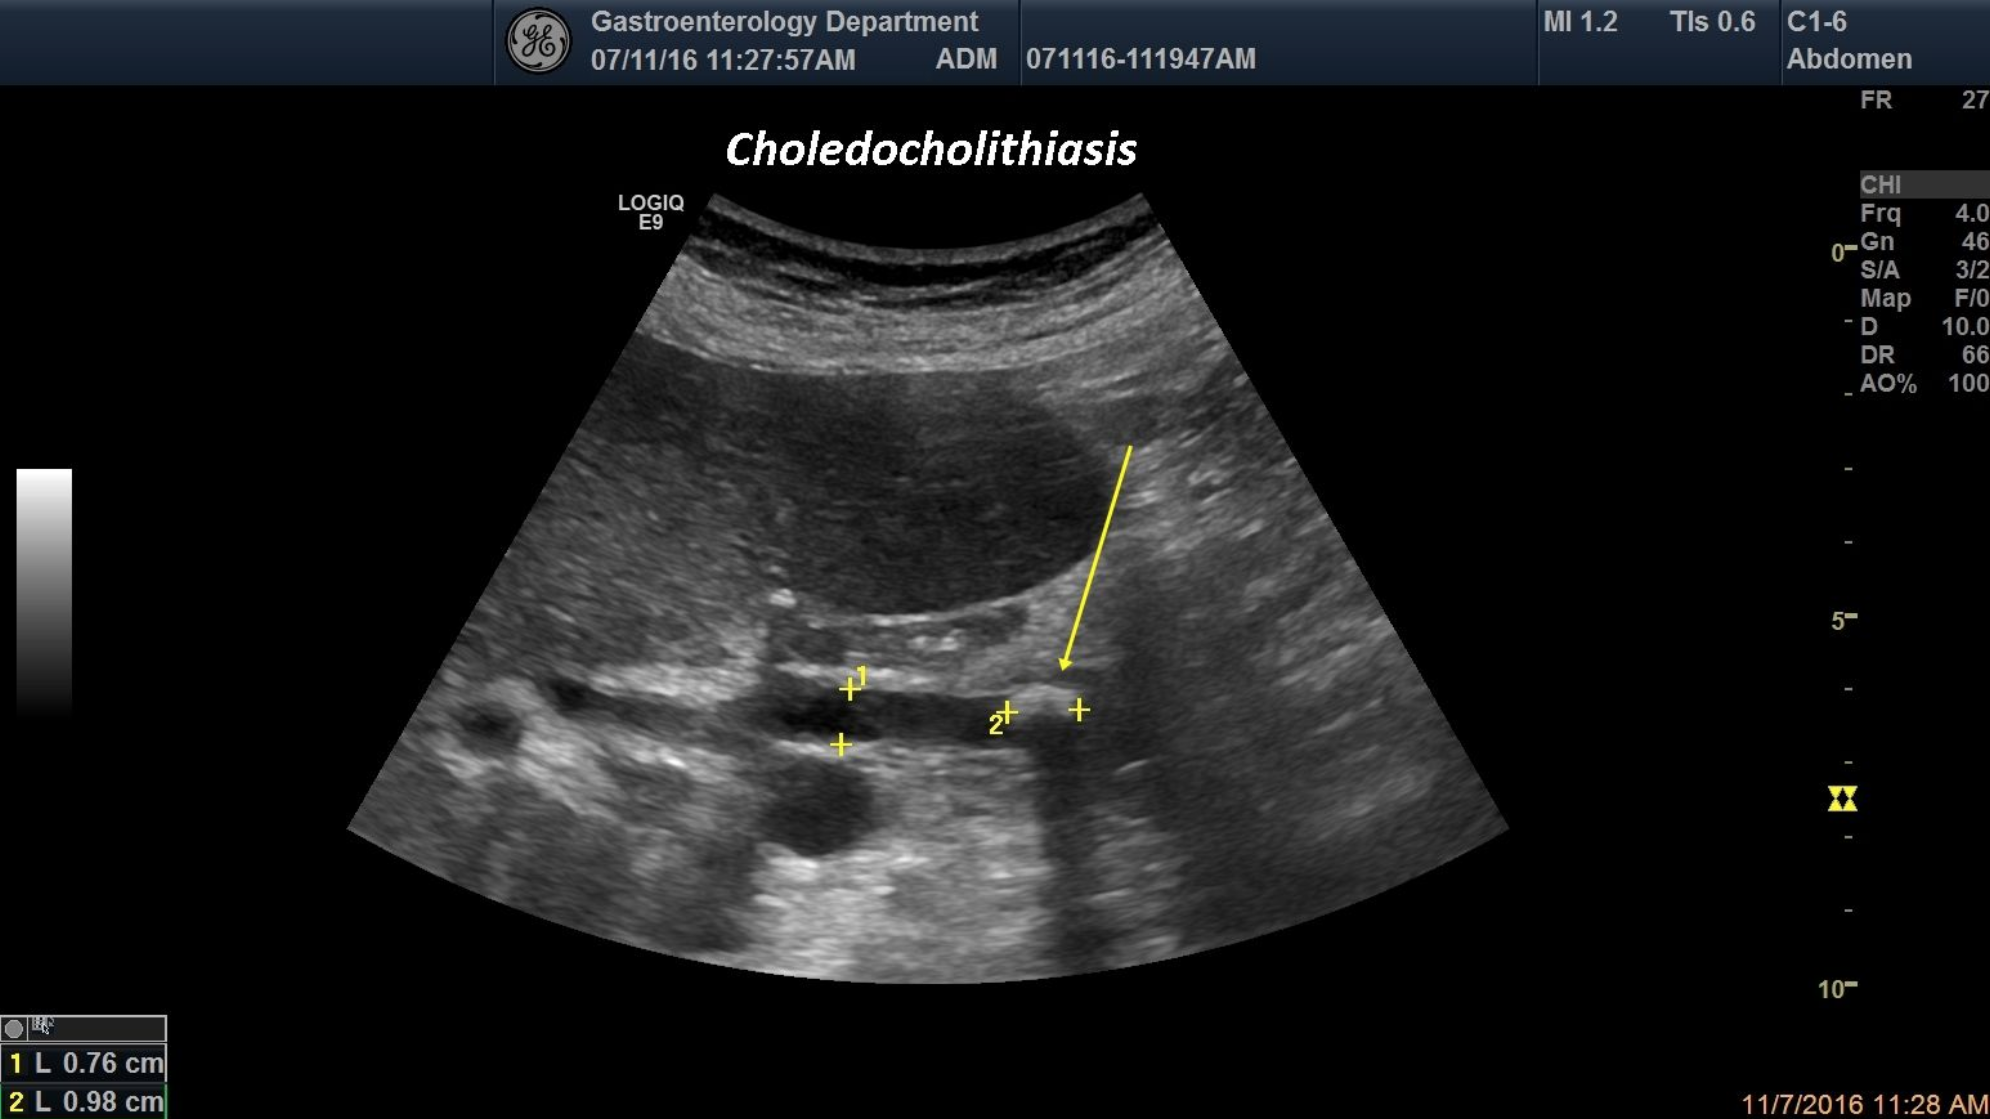

A 75-year-old patient was brought into the emergency room for jaundice and epigastric pain. Standard ultrasound depicted dilated CBD,a hyperechoic image with posterior shadowing inside the CBD and dilated biliary tree.

common bile duct, gallstones, obstructive jaundice, posterior shadowing